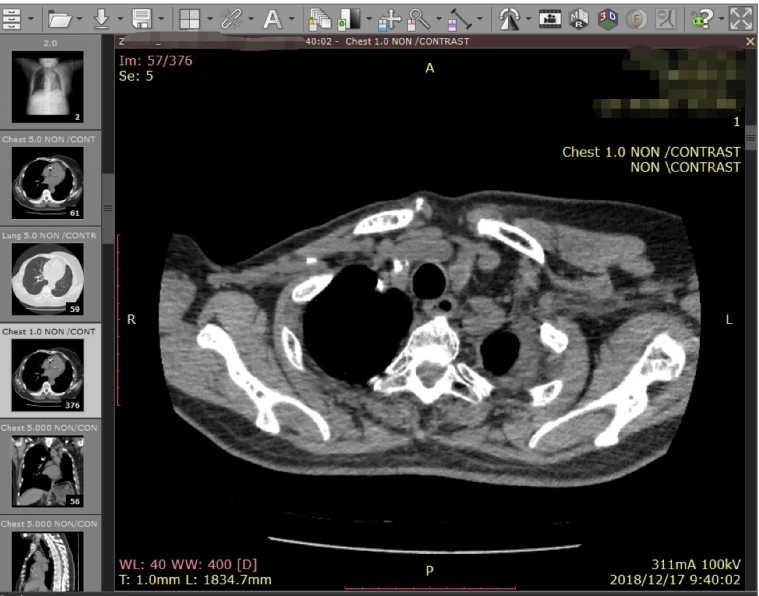

Dicom digital comfort

什么是DICOM格式医学影像?如何获取? - 哔哩哔哩